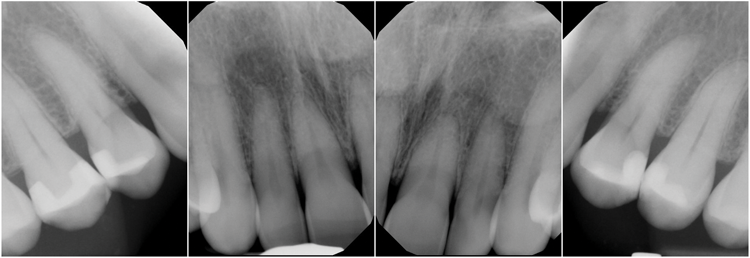

(5.) Preoperative radiographs of a female patient who presented with maxillary gingival recession and NCCLs.

Figure 5

A female patient presented to the practice with generalized gingival recession in the maxilla that extended from tooth No. 4 to tooth No. 13 (her maxillary first premolars were missing). The recession was classified as Cairo RT1 for all affected teeth, and the root exposure ranged from 1 mm to 4 mm. As part of the examination, radiographs were acquired; however, no remarkable interproximal bone loss was observed (Figure 5). Teeth Nos. 4, 6, 10, 11, and 13 were the most severely affected, and NCCLs were present on the canines and premolars (Figure 6). More specifically, tooth No. 4 presented with 3 mm of recession and an NCCL; tooth No. 6 presented with 3 mm of recession and an NCCL; teeth Nos. 7 through 9 presented with 1 mm of recession and no NCCLs; tooth No. 10 presented with 4 mm of recession and an NCCL; tooth No. 11 presented with 4 mm of recession and an NCCL; and finally, tooth No. 13 presented with 3 mm of recession and an NCCL. All of the NCCLs demonstrated a Winter and Allen classification of NCL3. The patient's keratinized tissue was greater than 2 mm for all teeth, her periodontal phenotype was thick, and her midline frenum was prominent and inserted 5 mm apical to the tip of the papilla between teeth Nos. 8 and 9.